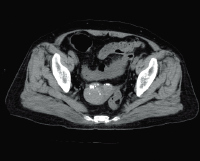

Клинические изображения

Для снижения лучевой нагрузки и повышения качества визуализации в КТ SUPRIA используются алгоритм интеллектуального перераспределения дозы IntelliEC и современный метод итерации IntelliIP, позволяющие провести сканирование с очень низкими значениями доз и получить изображения необходимого диагностического качества. В результате лучевая нагрузка на исследуемую область существенно снижается при сохранении высокого качества визуализации, особенно на уровне плотных паренхиматозных органов.